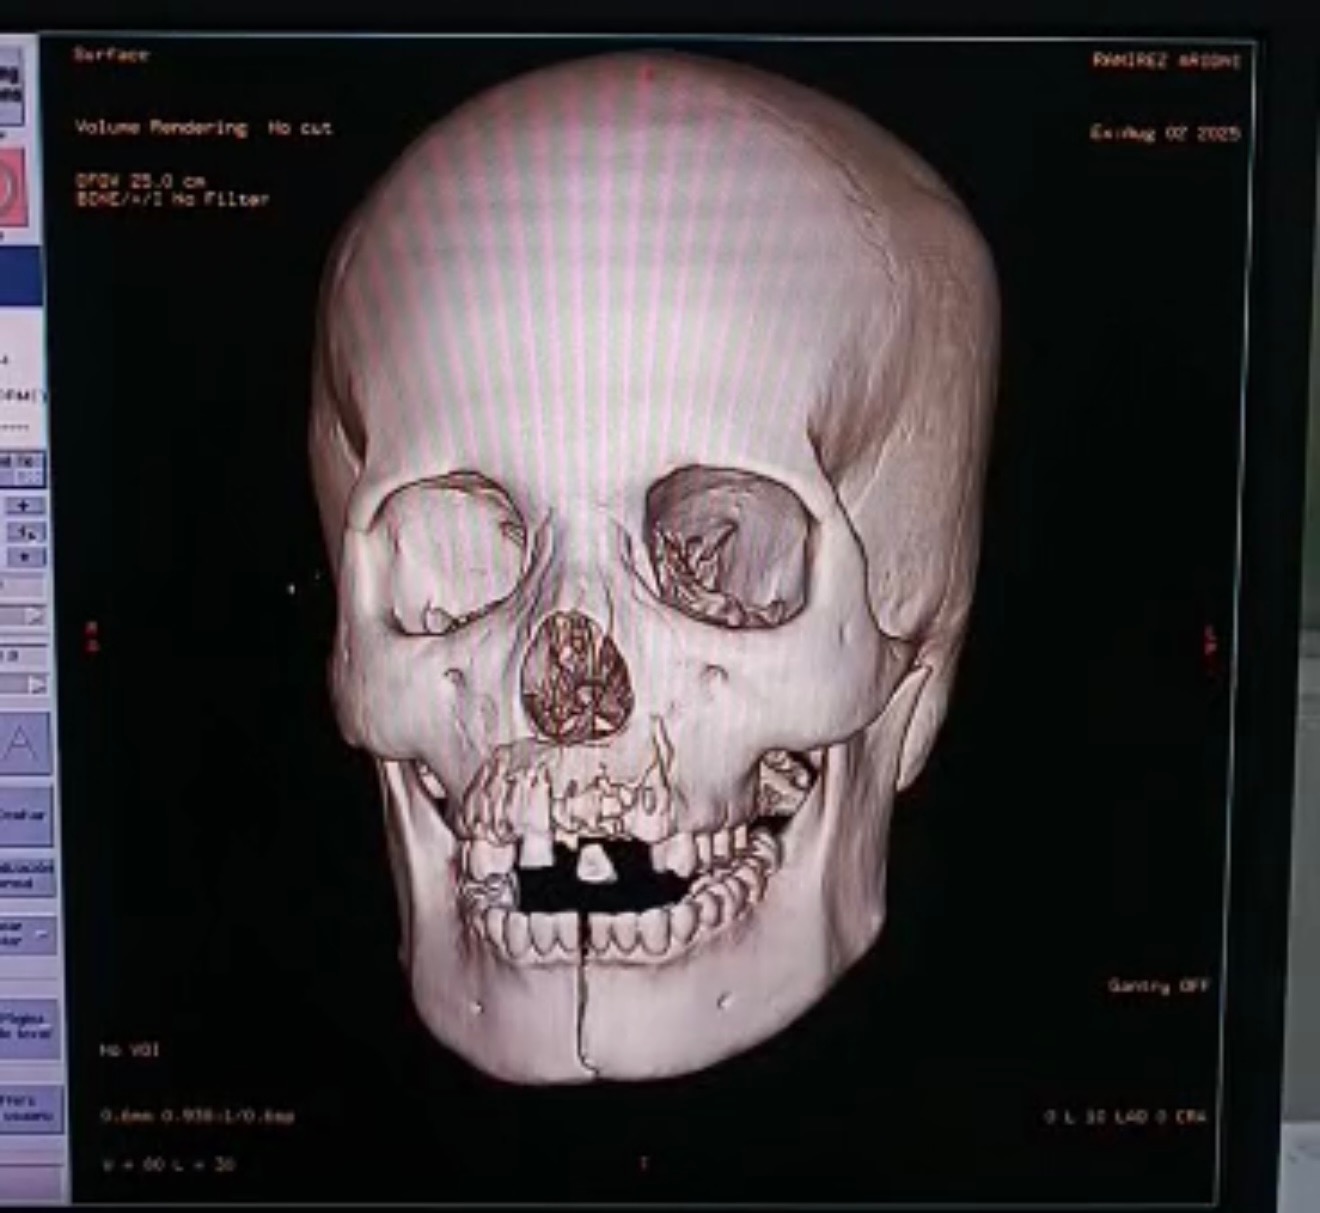

Hace poco, Aridni sufrió un grave accidente que le dejó múltiples lesiones: fractura grave de mandíbula, doble fractura de fémur, lesiones en el brazo y otras complicaciones que requieren atención médica urgente. Actualmente se encuentra en Venezuela, donde lamentablemente la salud pública atraviesa una crisis muy profunda. No hay insumos, quirófanos funcionales ni condiciones mínimas para que pueda ser operada en un hospital público.

La única opción viable es trasladarla a una clínica u hospital privado donde pueda recibir las cirugías que necesita para salvar su pierna, su mandíbula y su movilidad. Pero estos costos son altísimos. Yo soy su hermana mayor, la única de la familia que está fuera del país, y aunque hago todo lo posible por cubrir sus gastos, la situación me sobrepasa.